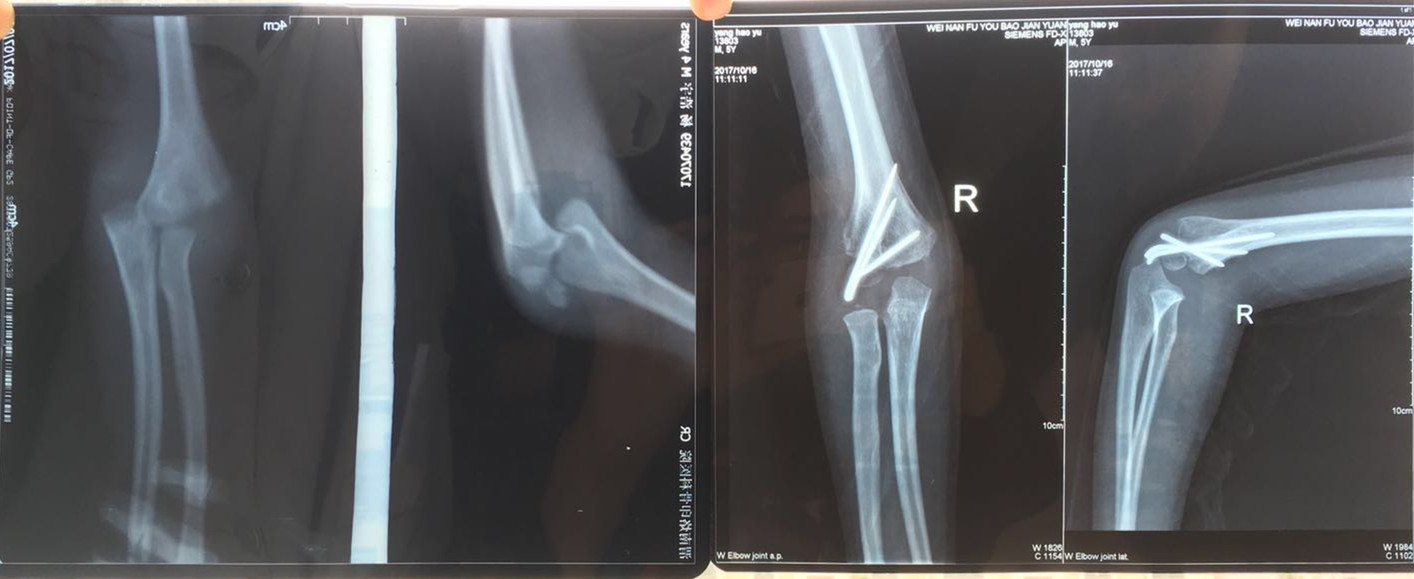

刘建军副主任医师接诊时,小西西疼痛难忍嚎啕大哭,根本不配合检查,抱着受伤的胳膊不让动,刘医生对小西西温言抚慰,趁孩子关注力转移时迅速进行手法复位石膏托固定,孩子的疼痛立即减轻,随后做了X线片和重建CT检查,诊断为:右侧肱骨外髁骨折并肘关节脱位。刘医生结合丰富的临床经验判断,单纯的手法复位治疗效果不佳,需要尽快做肘关节脱位切开复位内固定术进行治疗。

手术很快顺利完成,小西西住院一周后出院回家休养。在出院后定期复查时,刘建军副主任医师发现孩子肘关节功能恢复不佳,右侧肘关节不能屈曲伸直,就根据孩子的具体情况,耐心地指导家长帮助孩子进行功能锻炼,并多次进行电话跟踪随访治疗效果。

经过小儿外科医护人员精心的治疗和指导,加上小西西家长的积极配合,三个月后小西西再次来院复查时惊喜出现了,刘医生意外地发现伤情复杂严重的小西西肘关节功能恢复的竟然如此迅速和良好,已经可以取出内固定,随后再进行一段时间的康复锻炼,即可逐渐恢复肘关节正常的功能。